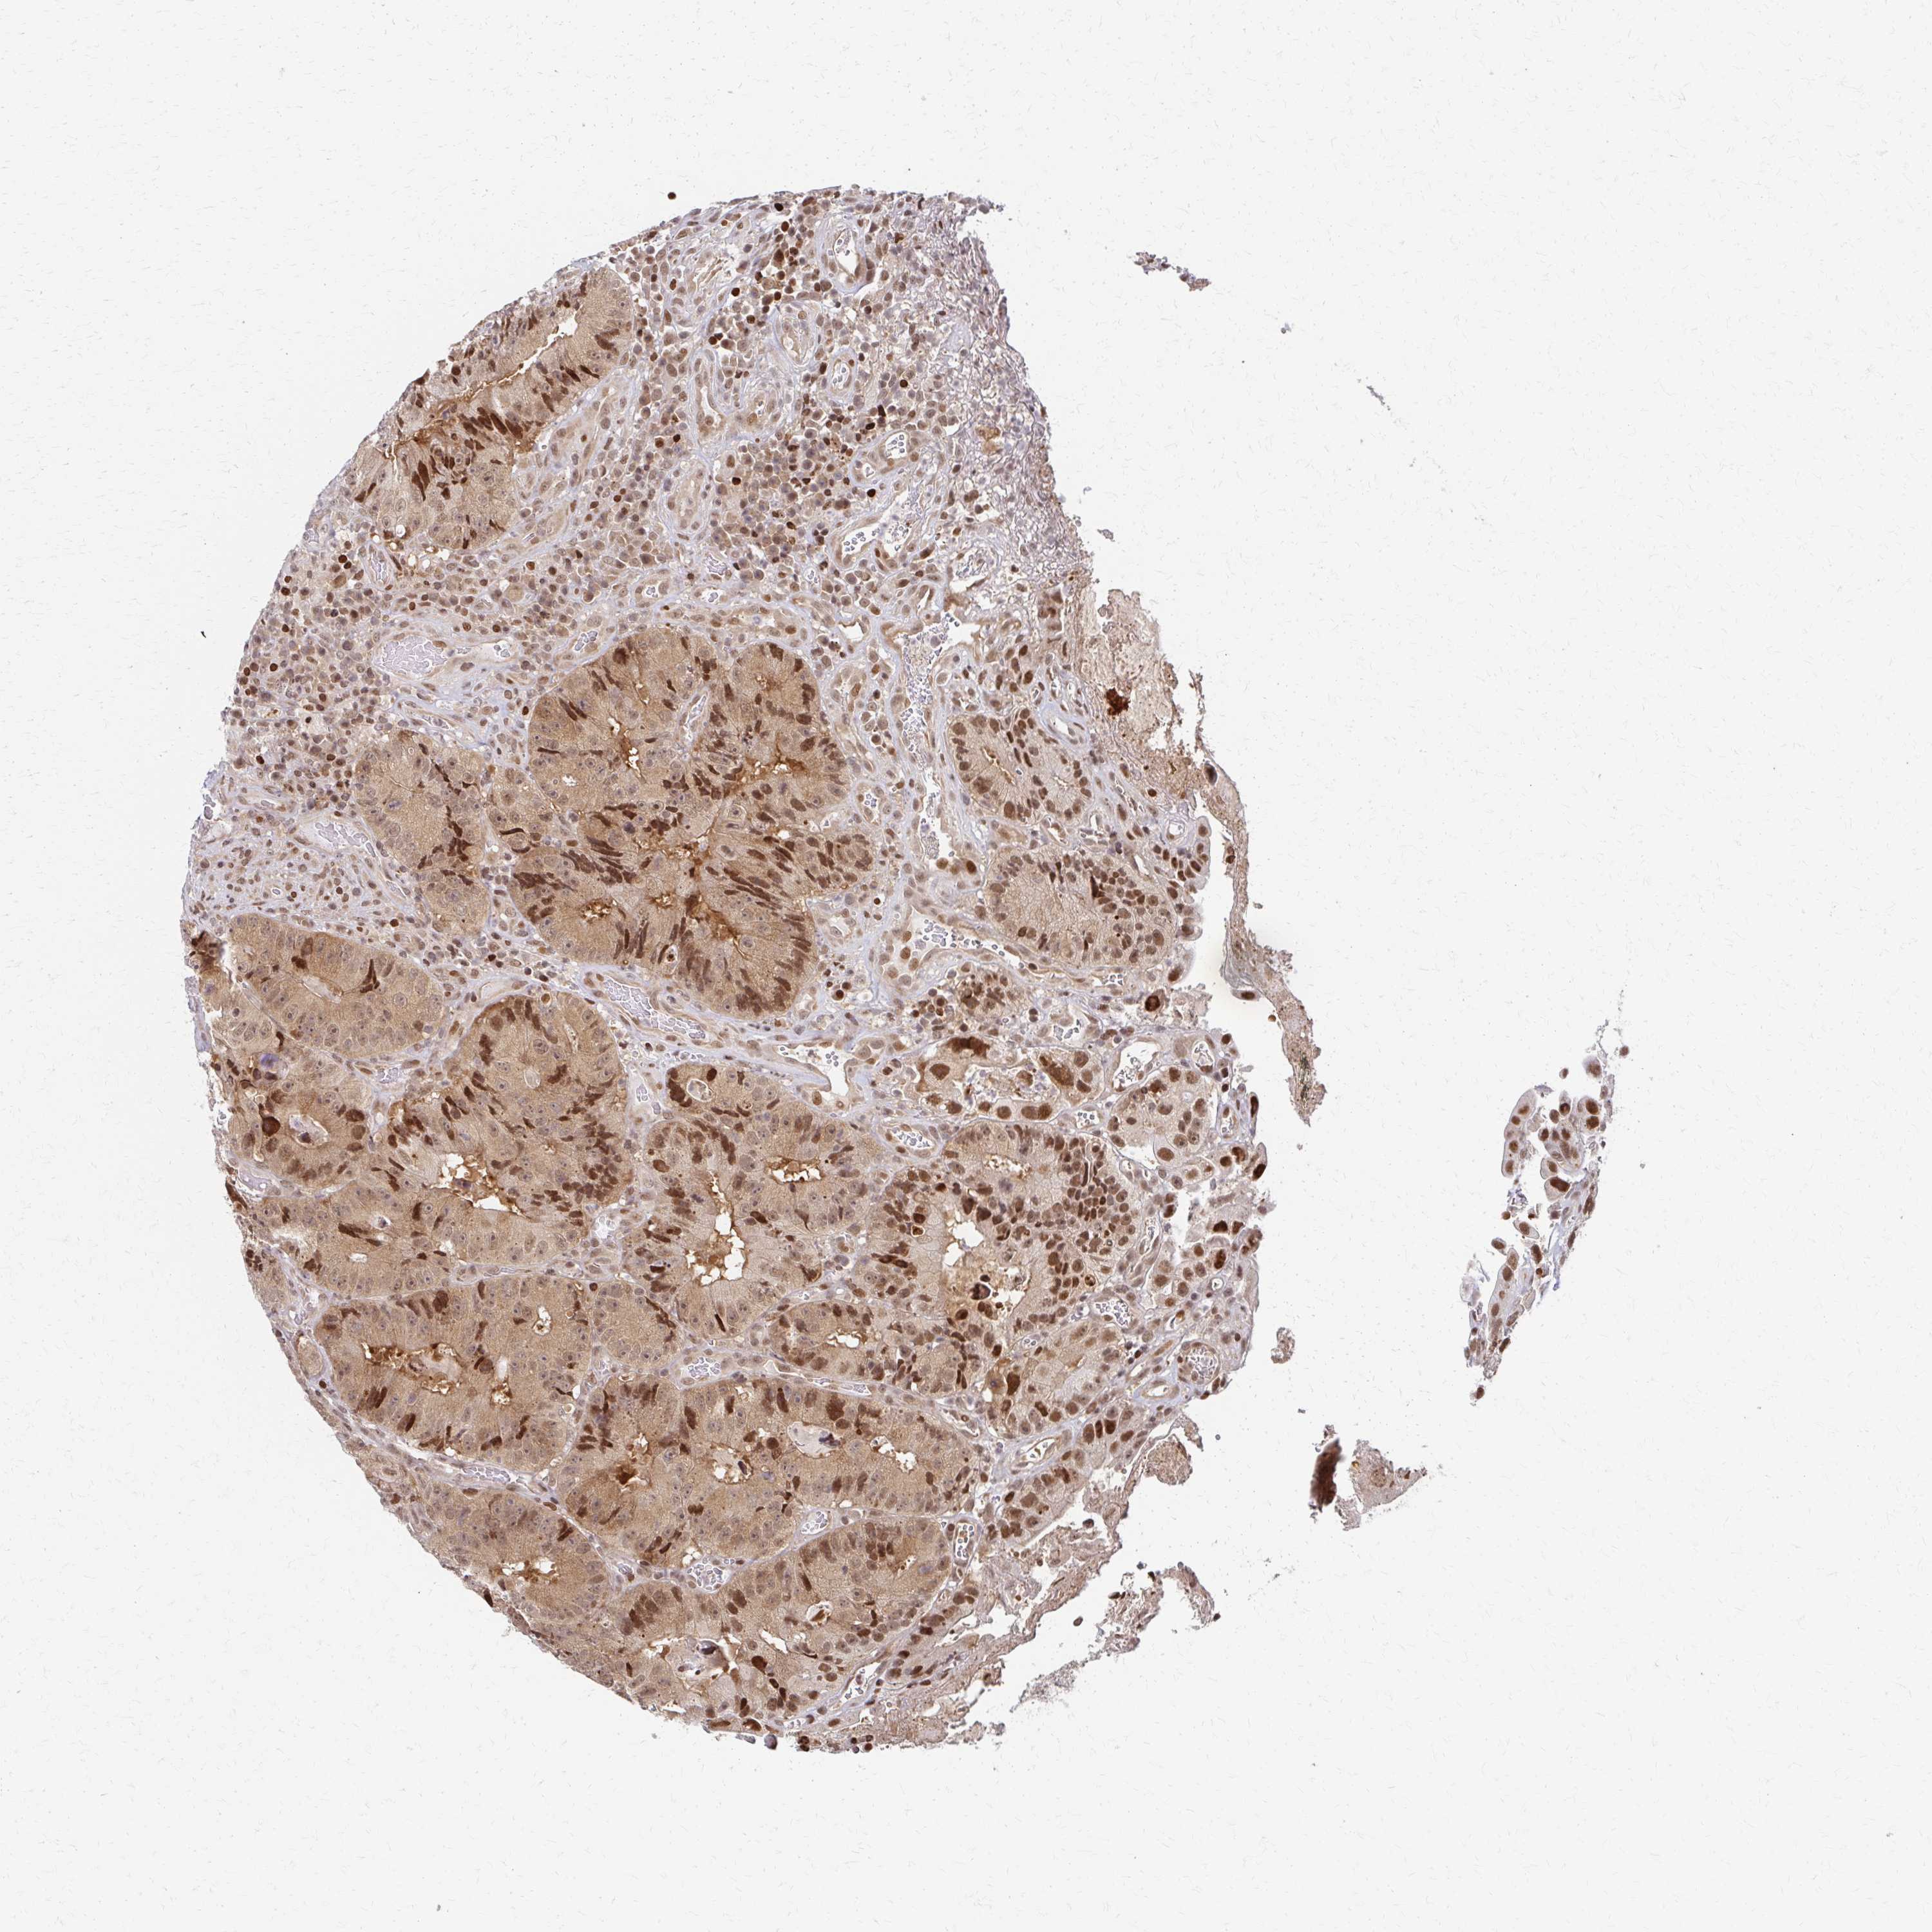

CANCER COLORECTAL CANCER Show tissue menu

Colorectal cancer

Human cancer

Colon adenocarcinoma